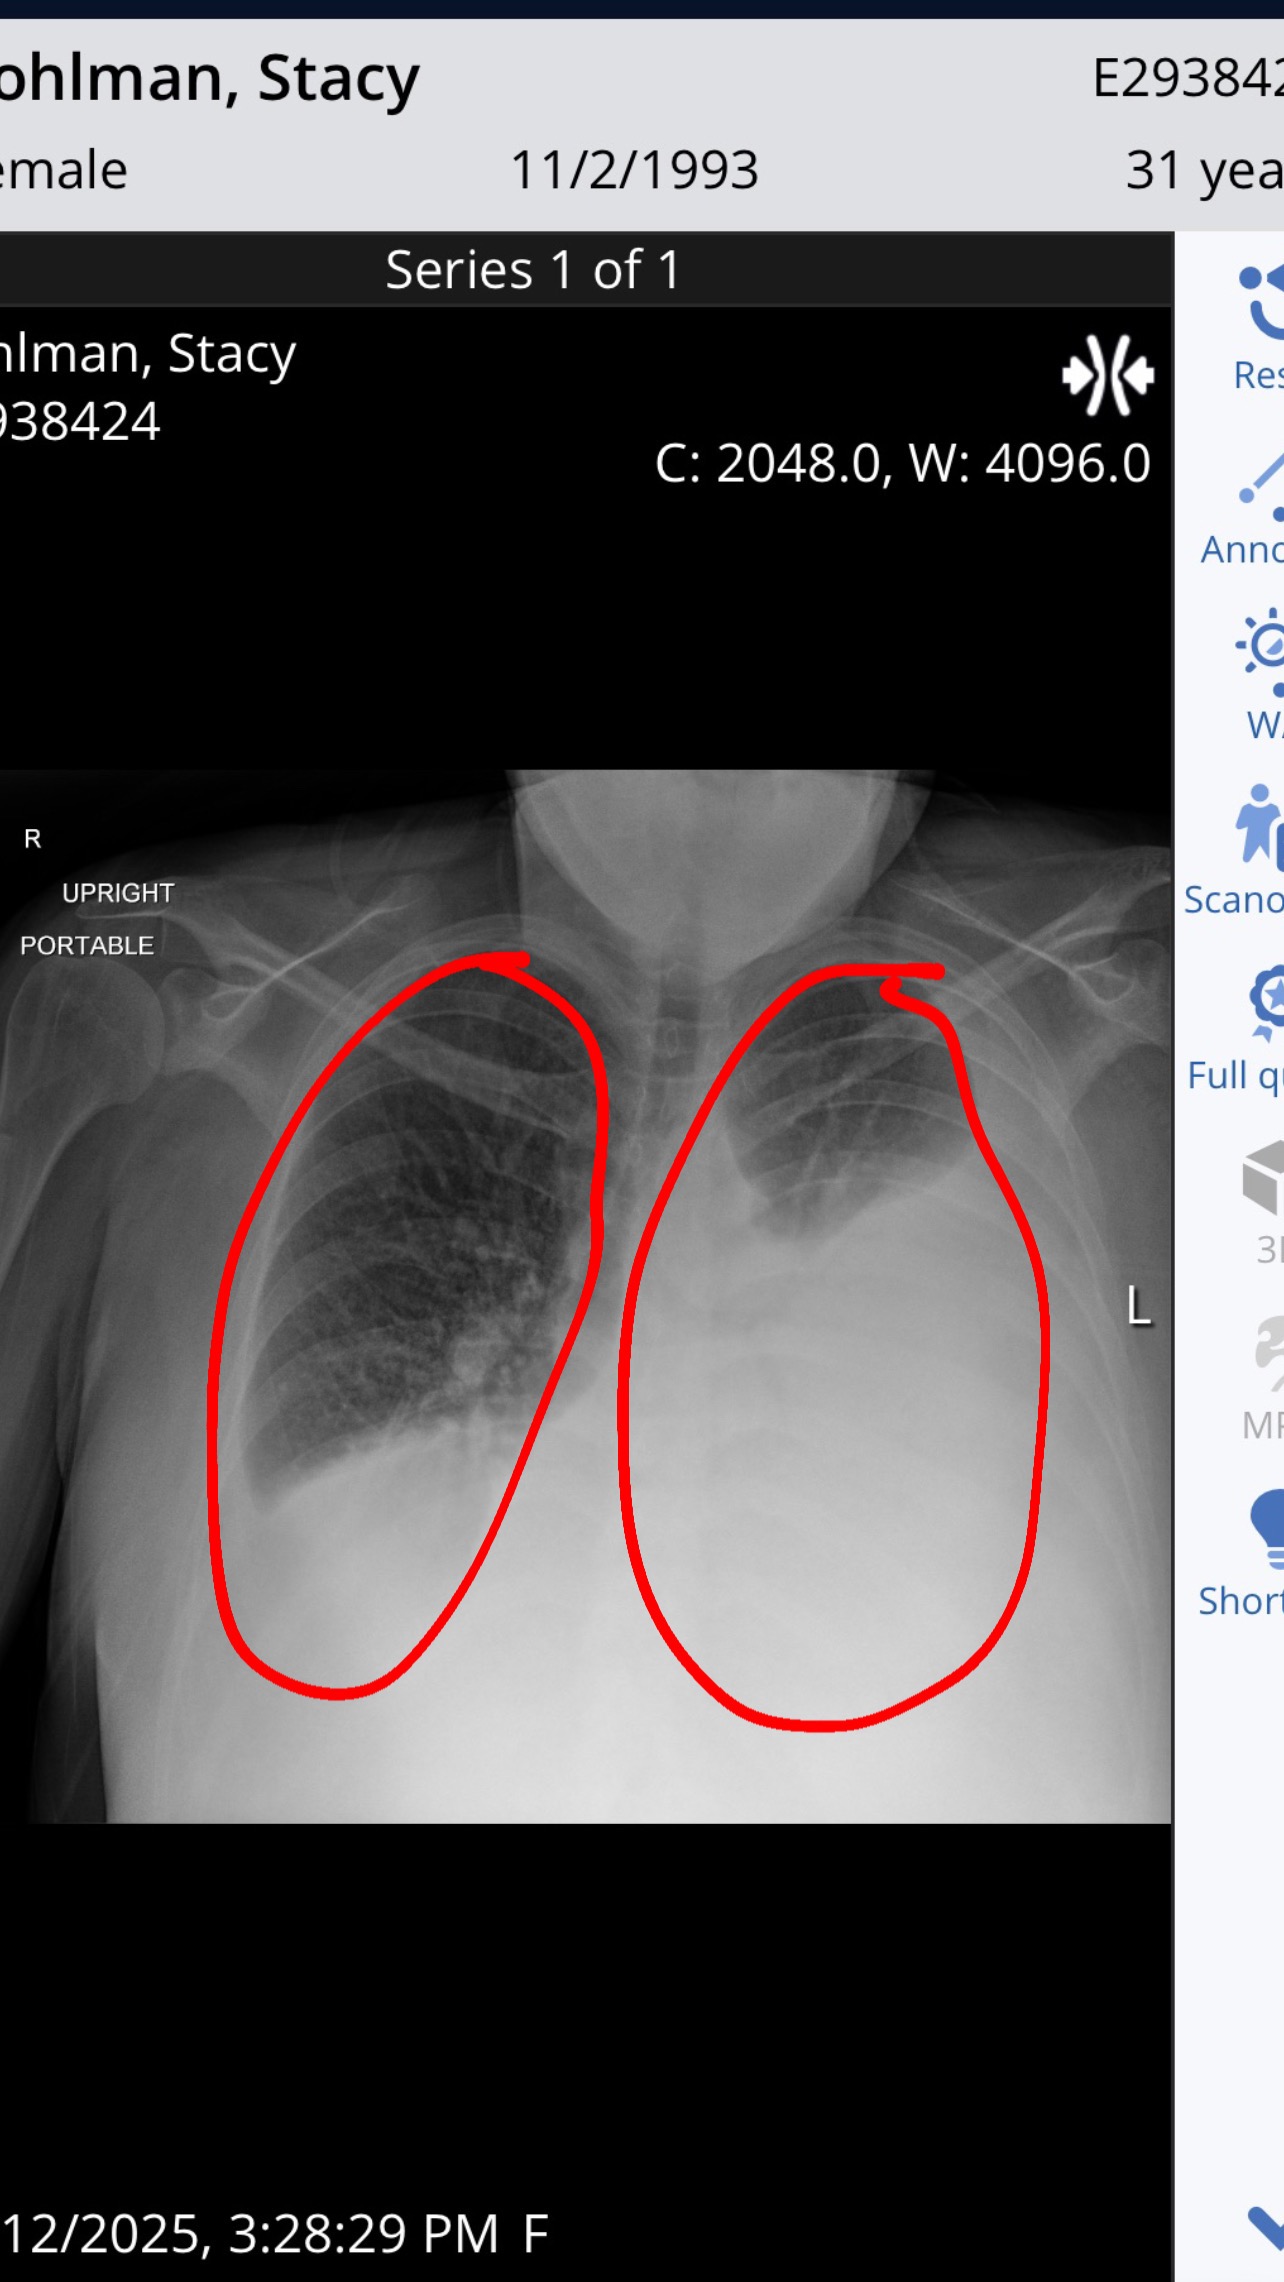

She was diagnosed with severe cirrhosis with portal hypertension and ascites. Her lungs filled with fluid — a massive pleural effusion — and now she needs oxygen 24/7 just to breathe.